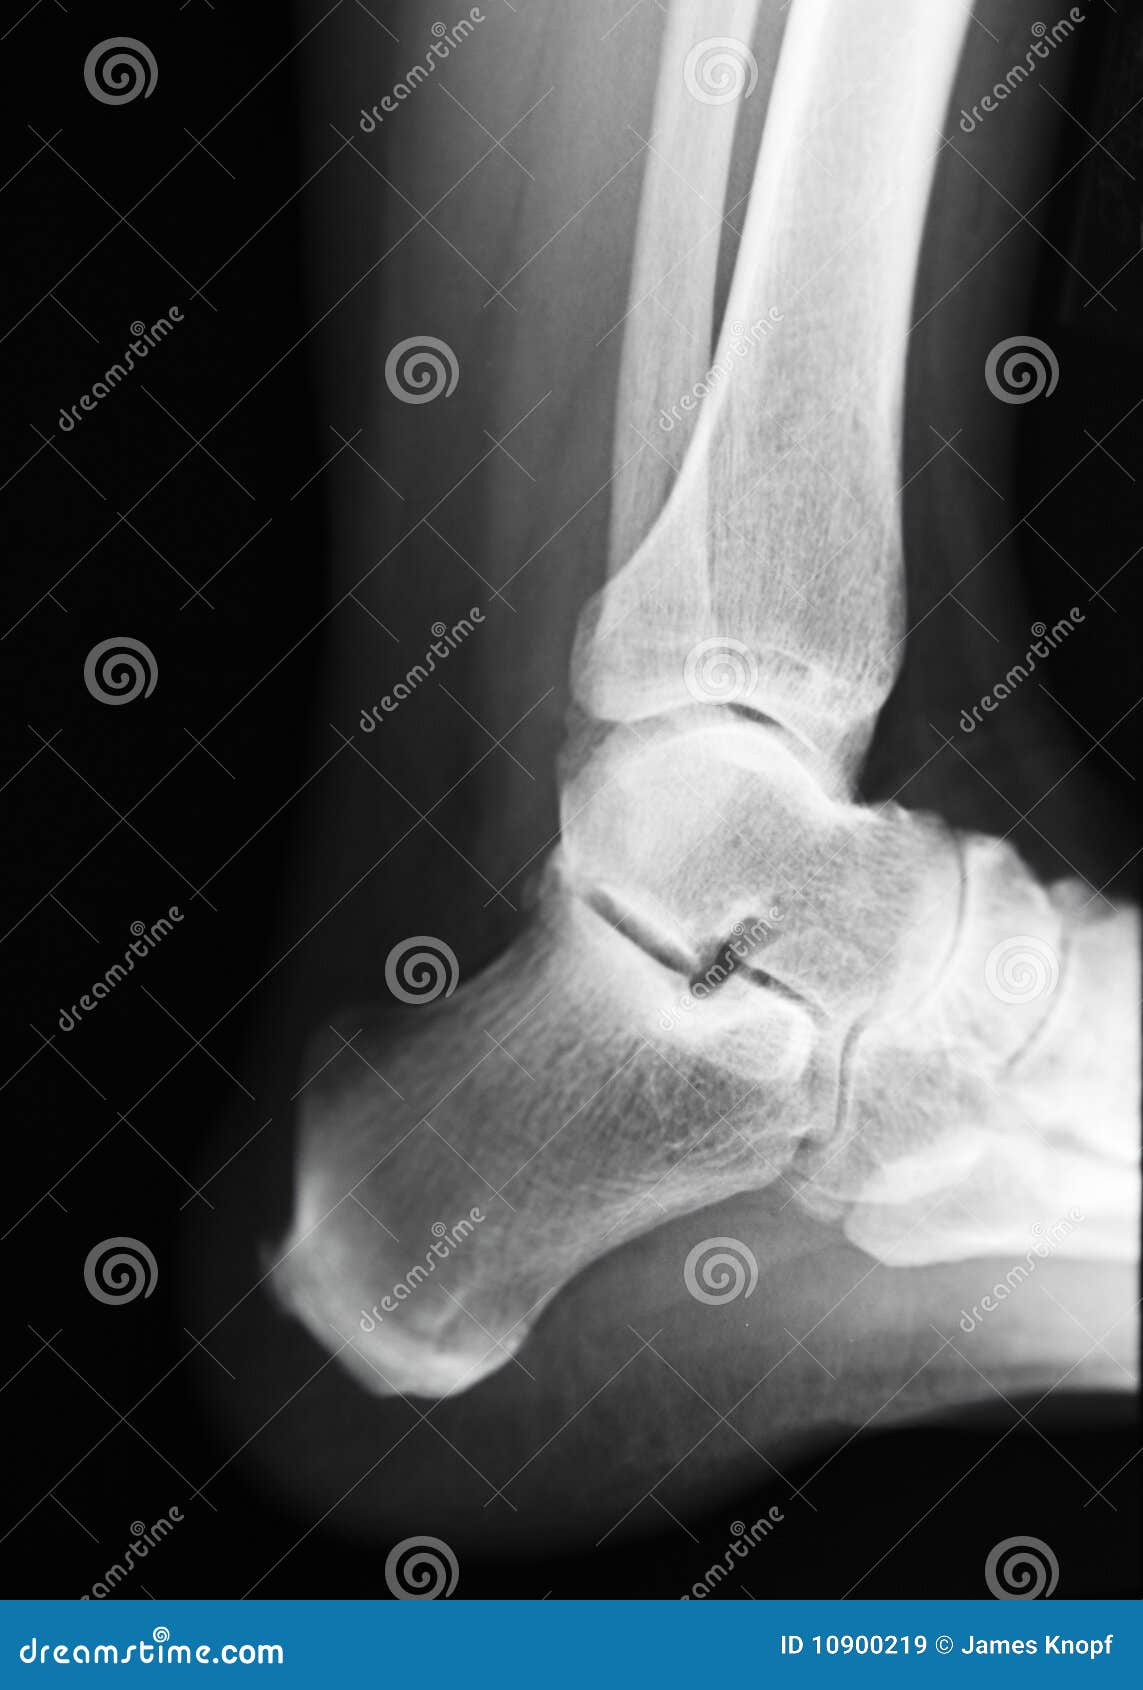

Frattura di calcagno - Dr. G. Fanzone

Frattura di calcagno - Dr. G. Fanzone from www.giuseppefanzone.it

Il calcagno è l'osso più grande del piede. La frattura del calcagno e' importante e va trattata bene (gesso o intervento)per i possibili effetti di mancato consolidamento e di dolore alla deambulazione. Per una frattura del femore basculamento arti superiori in opposizione agli inferiori. Per una frattura di bacino il paziente può perdere fino a 4l di sangue; Fratture da stress, o crepe nell'osso, devono essere adeguatamente trattate al fine di evitare una una caduta o movimenti ripetitivi martellante sull'osso del tallone possono portare a una frattura da. Una frattura del tallone porta a una procedura chirurgica chiamata osteosintesi , che aiuta a molte lesioni legate al piede o al tallone sono causate dalla pratica sportiva con attrezzature non adatte. Buongiorno, le fratture da stress sono per definizione più lunghe a guarire completamente. Nel corso del main event di daytona, aaron plessinger è caduto pesantemente rimediando la frattura del tallone. Quali sono i sintomi della frattura del tallone? La frattura del tallone è grave, di solito lascia sequel e ha una lunga guarigione e la persona potrebbe dover stare da 8 a 12 settimane senza essere in grado di sostenere il piede sul pavimento. Se vi capita spesso di sentire dolore al tallone del piede cambiando le scarpe, magari passando da quelle di tutti i giorni ad un paio eleganti, o dopo. La maggior parte delle fratture dell'osso del tallone derivano da impatti fisici o collisioni ad alta energia, secondo l'american academy of orthopaedic surgeons. Buongiorno e grazie per la vostra disponibilità. Quali sono le principali cause del male al tallone? Nozioni di base sulle fratture del tallone. Leggi la risposta del nostro specialista in fisioterapia, il cosa fare per un dolore al tallone dopo una frattura composta angolare del perone? Frattura del tallone si verifica meno frequentemente a causa di fattori specifici per questo tipo di danno.